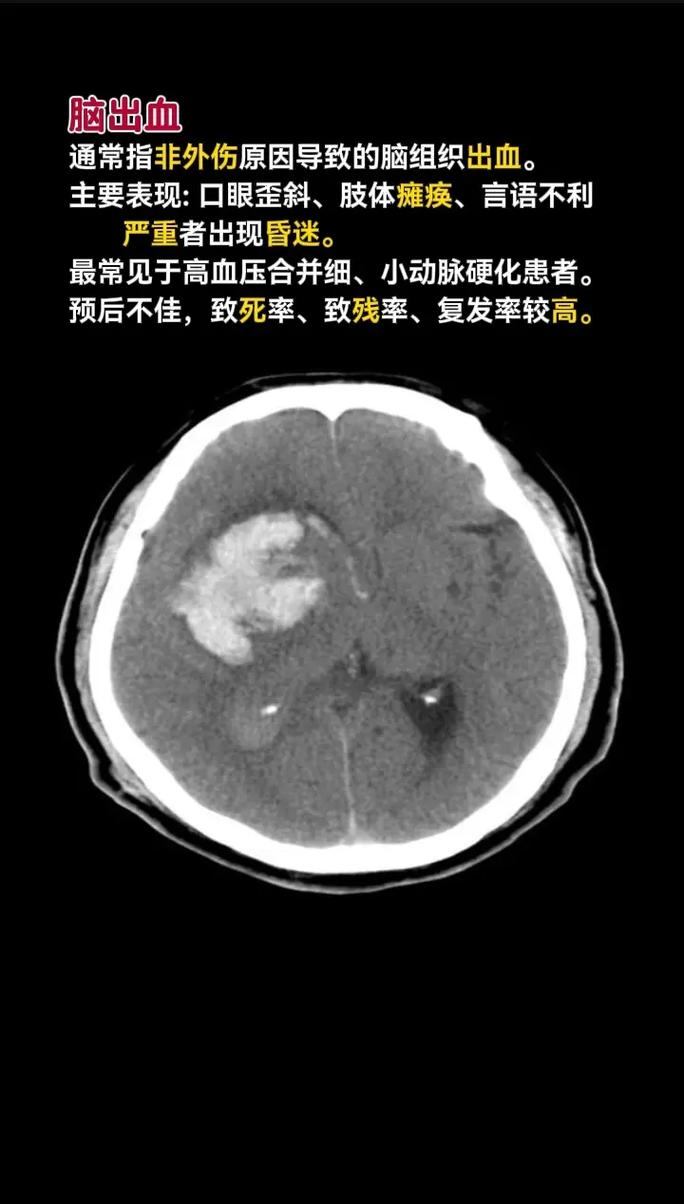

• 脑出血CT上能非常清晰地显示为高密度(白色)的“血肿”,像一块白色的污渍,这是诊断脑出血最快、最准确的方法。